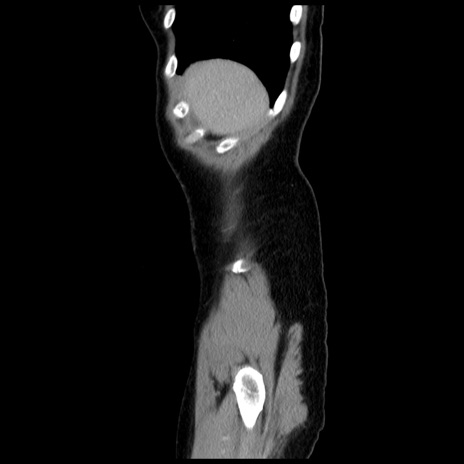

症例10(矢状断像)

症例

【症例】 50歳代女性

【主訴】 腹痛

【現病歴】前日生レバーを食べた。今朝に排便あり。 昼前に突然発症の腹痛を生じ、当院救急外来を受診した。

【既往歴】 子宮筋腫にてで子宮全摘後

【身体所見】 意識清明、腹部:平坦、軟、下腹部やや左を中心に圧痛・反跳痛あり、筋性防御あり

【データ】WBC 7800、CRP 0.07